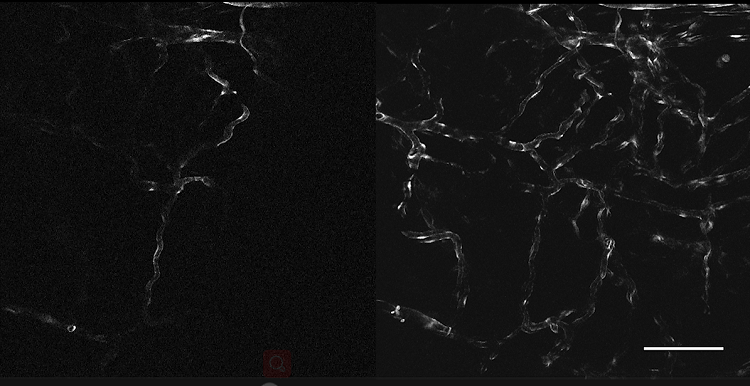

3、腫瘤血管生成OptiScan成像

左:正常皮膚微脈管系統(tǒng);右:黑色素瘤影響的皮膚微脈管系統(tǒng)。

注:活體CLE成像顯示無(wú)胸腺小鼠植入黑素瘤內(nèi)及周?chē)暮谒亓鱿嚓P(guān)脈管系統(tǒng)發(fā)生變化,靜脈注射(0.3 ml, 10 mg / ml)fitc-葡聚糖作為造影劑。Scale bar=100μm。